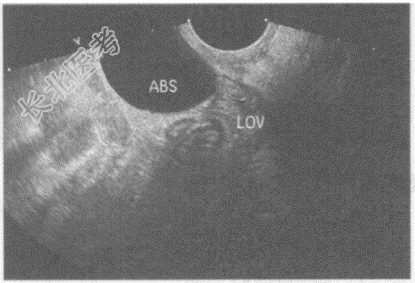

- 单项选择题临床资料:女性患者, 41岁,子宫全切术后。妇科内诊: 盆腔可触及肿物,质软。

超声综合描述: 经阴道扫查左附件区可见腊肠样无回声区,内透声清亮。

超声提示:  A、左卵巢囊肿

B、盆腔包裹性积液

C、左输卵管积水

D、左卵巢巧克力囊肿

E、左卵巢冠囊肿